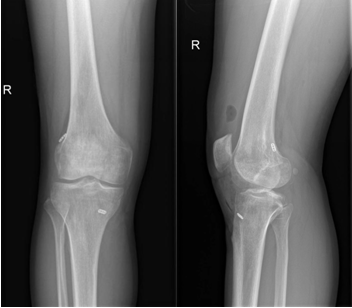

近日,一名31岁男性因打篮球扭伤致“右膝关节疼痛伴行走不稳半年”入院,术前诊断:前交叉韧带部分断裂。考虑患者年轻且有较高的运动恢复需求,在骨科病院刘时璋主任医师的指导下,由冯敏副主任医师主刀完成三级片

首例关节镜辅助下前交叉韧带损伤“保残+全内”重建术。患者第二日即下地活动,第三天顺利出院。